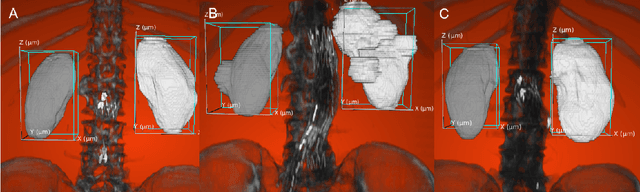

Organ localization can be challenging considering the heterogeneity of medical images and the biological diversity from one individual to another. The contribution of this paper is to overview the performance of the object detection model, YOLOv3, on kidney localization in 2D and in 3D from CT scans. The model obtained a 0.851 Dice score in 2D and 0.742 in 3D. The SSD, a similar state-of-the-art object detection model, showed similar scores on the test set. YOLOv3 and SSD demonstrated the ability to detect kidneys on a wide variety of CT scans including patients suffering from different renal conditions.